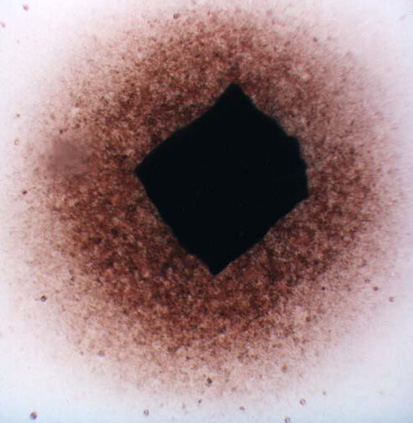

The migration activity of splenocytes [5] derived from rabbit spleen fragments was determined as follows. Aseptically excised rabbit (Chinchilla) spleen was cut on a sterile paraffin plate into pieces 1 mm in diameter. These fragments were washed in minimal essential medium (MEM). Increasing concentrations of the additives (photosensitizers, phthalhydrazide, CuSO4, H2O2) in MEM with 10% fetal calf serum (FCS) were pipetted in volumes of 0,2 mL into wells (plates 8x12, flat bottom). Each combination of the additives was placed into four wells; one fragment was transferred into each well. The fragments in cultivation medium only were used as a control. After 24 hours of cultivation at 37oC in 5% CO2, the migration zones of the spleen cells were measured [5]. The results are presented as the migration index (MI) - the ratio between the experimental migration zone (Fig.I.B.) to the control zone (Fig.I.A.). Compounds were tested in two independent experiments in triplicate.

Figure I. Fragments of the rabbit's spleen splenocytes

A. …………………………………………………………………..B.

………………………………………..

As a first

we confirmed that the photosensitizers chemiexcited by phthalhydrazide can produce the photodynamic damage on the rabbit’s spleen (test of vitality of the migration activity of splenocytes derived from rabbit's spleen fragments).This test turned up to be the simple, versatile and reliable for photodynamic effect in connection with sensitized chemiluminescence. For the dependence on the elementary concentrations of the photosensitizer, compounds of the chemiluminescent system and on their combinations, the data display the changes of the migration index. The changes can be neglected for the compounds of the chemiluminescent system but they are significant for the individual photosensitizer and its combination with the chemiluminescent compounds. Dependencies of MI on the photosensitizer concentration, eventually on the photosensitizer concentration at the presence of compounds of the chemiluminescent system, complied with simple Langmuir isotherms. For this reason we were able to assume that photosensitizer is adsorbed in the biological membrane and the presented data indicate that observed lethality is a result of photodynamic effect.